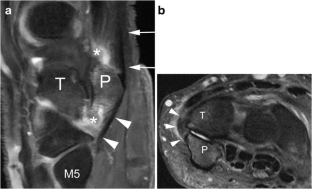

Pisotriquetral joint disorders: an under-recognized cause of ulnar side wrist pain

Pisotriquetral joint disorders are often under-recognized in routine clinical practice. They nevertheless represent a significant cause of ulnar side wrist pain. The aim of this article is to present the main disorders of this joint and discuss the different imaging modalities that can be useful for its assessment.